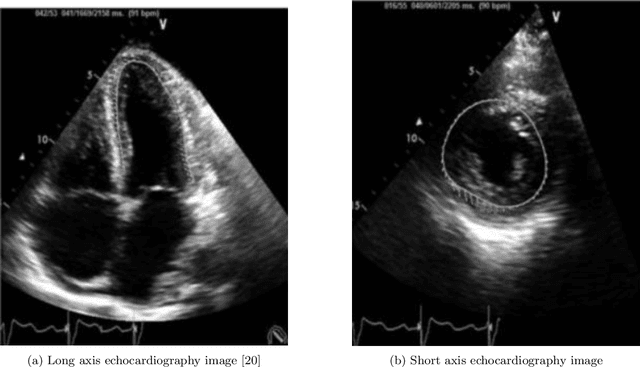

Abstract:Image registration is used in many medical image analysis applications, such as tracking the motion of tissue in cardiac images, where cardiac kinematics can be an indicator of tissue health. Registration is a challenging problem for deep learning algorithms because ground truth transformations are not feasible to create, and because there are potentially multiple transformations that can produce images that appear correlated with the goal. Unsupervised methods have been proposed to learn to predict effective transformations, but these methods take significantly longer to predict than established baseline methods. For a deep learning method to see adoption in wider research and clinical settings, it should be designed to run in a reasonable time on common, mid-level hardware. Fast methods have been proposed for the task of image registration but often use patch-based methods which can affect registration accuracy for a highly dynamic organ such as the heart. In this thesis, a fast, volumetric registration model is proposed for the use of quantifying cardiac strain. The proposed Deep Learning Neural Network (DLNN) is designed to utilize an architecture that can compute convolutions incredibly efficiently, allowing the model to achieve registration fidelity similar to other state-of-the-art models while taking a fraction of the time to perform inference. The proposed fast and lightweight registration (FLIR) model is used to predict tissue motion which is then used to quantify the non-uniform strain experienced by the tissue. For acquisitions taken from the same patient at approximately the same time, it would be expected that strain values measured between the acquisitions would have very small differences. Using this metric, strain values computed using the FLIR method are shown to be very consistent.